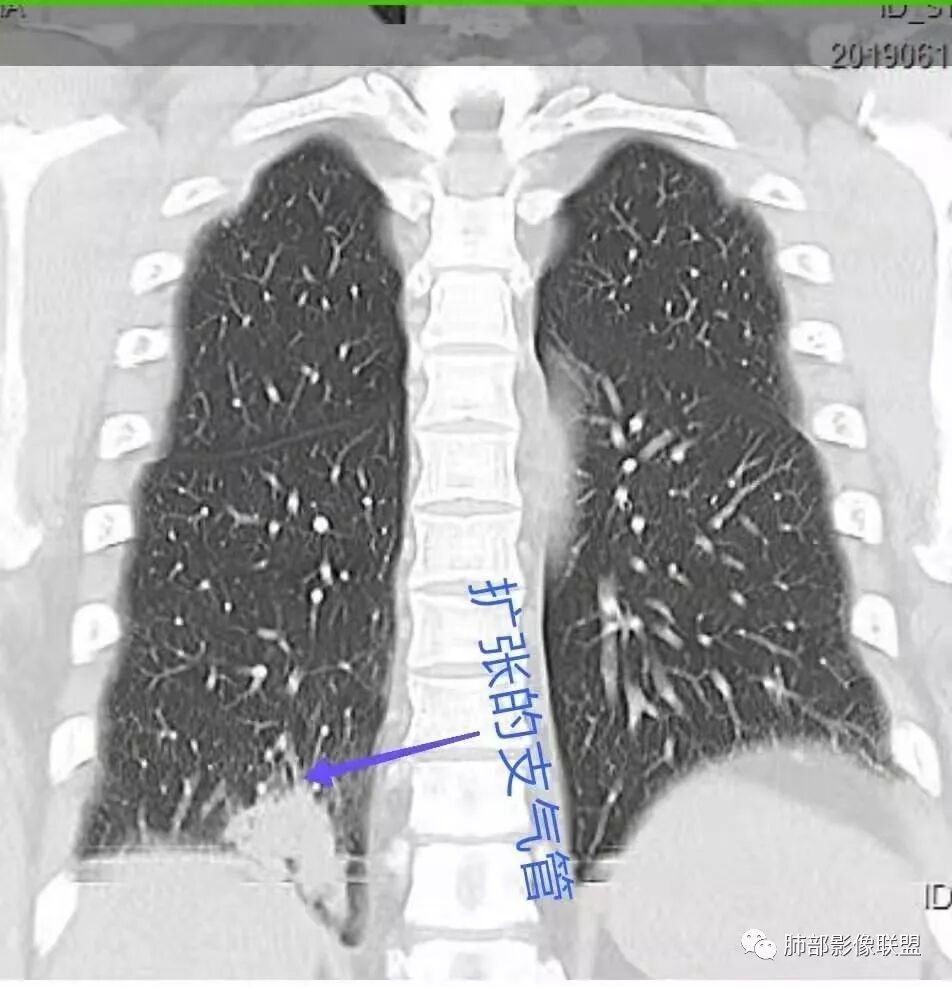

患者男,45岁,因乏力、低热、心悸入院,最高体温38℃,偶有咳嗽、无咳痰、咯血,肿瘤标志物阴性。

影像资料

中年男性,乏力  低热入院,胸CT:右肺下叶后基底段结节样病变,病灶周围可见细支气管扩张,病灶边缘可见短软毛刺,病灶周围有毛玻璃影,冠状位肺窗病灶与膈胸膜呈宽基地,纵隔窗可见病灶内空洞及低密度区,增强明显强化及延迟强化,考虑良性感染性病变,隐球菌肺炎?,结核?。但在冠状位肺窗有一支细支气管在病灶旁有截断,还得除外肺癌的可能性。

中年男性,以低热、乏力为主要症状,右下叶近胸膜病灶,支气管进入但有近端堵塞,周围有短毛刺,磨玻璃影边界不清,周边有条索状纤维灶,病灶有强化和点状坏死,考虑炎性肉芽肿可能性大,隐球?目前整体考虑炎性,但具体是啥是猜的。

右肺下叶后基底段结节,边缘较清,有浅分叶,病灶长轴与胸膜平形,以平直收缩为主,局部稍膨隆,有长短不一的毛刺,边缘模糊,周围有小片状模糊hggo,中心有小空泡或小空 洞,内壁光整,增强后延迟强化,提示会不会有纤维组织成份,而且空腔内壁强化明显且完整,邻近胸膜有糊墙,考虑炎性病变,机化性肺炎合并脓肿?鉴别癌。

影像特点:多灶实变(多为双侧非对称性分布,部分病灶有一定的游走性)、单发或多发结节、反晕征。

分布特点:胸膜下和沿支气管血管束分布、条带状实变、小叶旁实变。

3.部分可见支气管管像,但很少支气管截断。